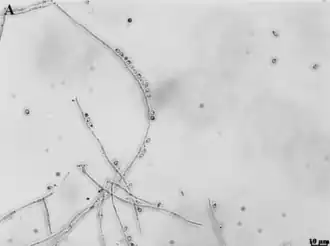

S. brasiliensis, Hefezellen in typisch | ||||||||||||

Sporothrix brasiliensis weist zwei Morphologien auf: eine Hyphenform, die in der Umwelt (Boden) vorkommt, und eine Hefeform, die bei höheren Temperaturen wie im Körper von Säugetieren (36–37 °C) vorkommt.

Hyphenphase

Die Hyphenform von S. brasiliensis tritt bei Raumtemperatur auf. Der Grad der Melaninisierung (Färbung, Dunkelfärbung) der Hyphenform kann von hellen („albino“) bis zu dunklen („pigmentiert“) Phänotypen reichen. Sympodiale Konidien sind obovoid (eiförmig) und haben ein glasiges (hyalines) Aussehen, während sessile Konidien dunkel gefärbt und kugelförmig sind.[4]